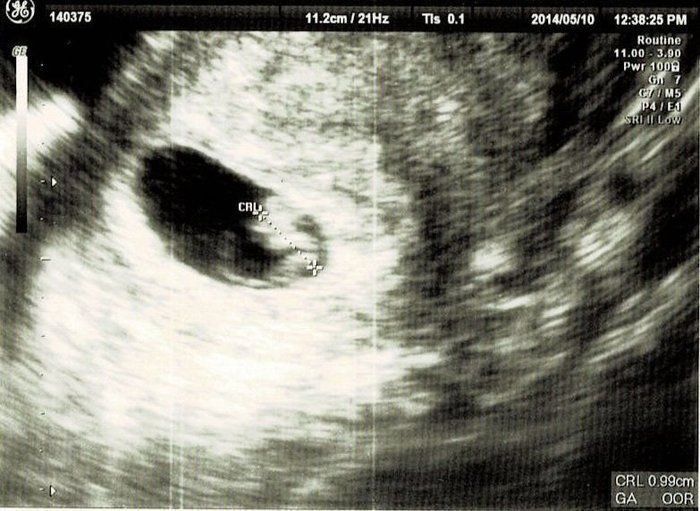

ベビオママさんの妊娠8週目のエコー写真 予定日が確定!

真ん中の胎嚢の中に、小さな赤ちゃんが写っています。エコーで初めて赤ちゃんが手足をちょこちょこ動かしているところを見ることができ、とってもかわいかったです。ゴールデンウィークの間、体を休めて横になっていることが多かったので少し太りました。休みが終わって仕事を再開すると、気持ちが悪くて吐いてしまうことが増え、特に忙しい時に体調が悪化しやすいようでした。母の日に、夫がピンクのカーネーションをくれました。思いがけないサプライズで嬉しかったです。